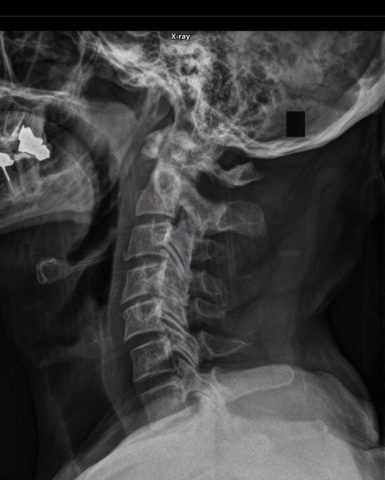

Π€ΠΎΡΠΎ: Π°Π½Π°ΡΠΎΠΌΠΈΡΠ΅ΡΠΊΠΈΠ΅ Ρ Π°ΡΠ°ΠΊΡΠ΅ΡΠΈΡΡΠΈΠΊΠΈ ΡΡΠ°Π²ΠΌΡ ΡΠ΅ΠΉΠ½ΠΎΠ³ΠΎ ΠΎΡΠ΄Π΅Π»Π° ΠΏΠΎΠ·Π²ΠΎΠ½ΠΎΡΠ½ΠΈΠΊΠ°

ΠΠ»Ρ ΠΏΠΎΠ΄ΡΠ²Π΅ΡΠΆΠ΄Π΅Π½ΠΈΡ Π΄ΠΈΠ°Π³Π½ΠΎΠ·Π° ΠΏΡΠΎΠ²ΠΎΠ΄ΡΡΡΡ ΡΠΏΠ΅ΡΠΈΠ°Π»ΡΠ½ΡΠ΅ ΠΏΡΠΎΡΠ΅Π΄ΡΡΡ, ΡΡΠ΅Π΄ΠΈ ΠΊΠΎΡΠΎΡΡΡ Π½Π°ΠΈΠ±ΠΎΠ»Π΅Π΅ ΠΈΠ½ΡΠΎΡΠΌΠ°ΡΠΈΠ²Π½ΡΠΌΠΈ ΡΡΠΈΡΠ°ΡΡΡΡ ΡΠ΅Π½ΡΠ³Π΅Π½ΠΎΠ³ΡΠ°ΡΠΈΡ ΠΈ ΠΊΠΎΠΌΠΏΡΡΡΠ΅ΡΠ½Π°Ρ ΡΠΎΠΌΠΎΠ³ΡΠ°ΡΠΈΡ. ΠΠΎΠΏΠΎΠ»Π½ΠΈΡΠ΅Π»ΡΠ½ΡΠ΅ Π°Π½Π°Π»ΠΈΠ·Ρ ΠΈ ΠΈΡΡΠ»Π΅Π΄ΠΎΠ²Π°Π½ΠΈΡ Π½Π°Π·Π½Π°ΡΠ°ΡΡΡΡ Π² Π·Π°Π²ΠΈΡΠΈΠΌΠΎΡΡΠΈ ΠΎΡ ΠΏΠΎΠ΄ΠΎΠ·ΡΠ΅Π²Π°Π΅ΠΌΡΡ ΠΎΡΠ»ΠΎΠΆΠ½Π΅Π½ΠΈΠΉ.

ΡΠ΅Π±Π΅Ρ Ρ ΡΠ΅ΡΠ΅ΠΏΠΎΠΌ, Π° ΠΏΠΎΠ·Π²ΠΎΠ½ΠΎΡΠ½ΠΈΠΊ Ρ Π·Π°ΡΡΠ»ΠΎΡΠ½ΠΎΠΉ ΠΊΠΎΡΡΡΡ. ![]() Π Π΅Π½ΡΠ³Π΅Π½ΠΎΠ»ΠΎΠ³ΠΈΡΠ΅ΡΠΊΠΈΠΉ ΡΠ½ΠΈΠΌΠΎΠΊ Π½Π°ΡΡΡΠ΅Π½Π½ΠΎΠΉ ΡΠ΅Π»ΠΎΡΡΠ½ΠΎΡΡΠΈ ΠΏΠ΅ΡΠ²ΠΎΠ³ΠΎ ΡΠ΅ΠΉΠ½ΠΎΠ³ΠΎ ΠΏΠΎΠ·Π²ΠΎΠ½ΠΊΠ° Π’ΡΠ°Π²ΠΌΠ° Π² Π΄Π°Π½Π½ΠΎΠΉ ΠΎΠ±Π»Π°ΡΡΠΈ ΡΠΎΠΏΡΠΎΠ²ΠΎΠΆΠ΄Π°Π΅ΡΡΡ ΠΏΠΎΠ»Π½ΠΎΠΉ ΠΈΠ»ΠΈ ΡΠ°ΡΡΠΈΡΠ½ΠΎΠΉ ΠΏΠΎΡΠ΅ΡΠ΅ΠΉ ΡΡΠ²ΡΡΠ²ΠΈΡΠ΅Π»ΡΠ½ΠΎΡΡΠΈ ΠΎΡΠ³Π°Π½ΠΎΠ², ΠΏΡΠΈΠ½Π°Π΄Π»Π΅ΠΆΠ°ΡΠΈΡ ΠΊ ΠΎΠΏΠΎΡΠ½ΠΎ-Π΄Π²ΠΈΠ³Π°ΡΠ΅Π»ΡΠ½ΠΎΠΉ ΡΠΈΡΡΠ΅ΠΌΠ΅. |

Π§ΡΠΎΠ±Ρ ΠΎΠΏΡΠ΅Π΄Π΅Π»ΠΈΡΡ ΠΏΠ΅ΡΠ΅Π»ΠΎΠΌ ΡΠ΅ΠΉΠ½ΡΡ ΠΏΠΎΠ·Π²ΠΎΠ½ΠΊΠΎΠ² Π±ΠΎΠ»ΡΠ½ΠΎΠΌΡ Π΄Π΅Π»Π°ΡΡ ΡΠ΅Π½ΡΠ³Π΅Π½ΠΎΠ»ΠΎΠ³ΠΈΡΠ΅ΡΠΊΠΎΠ΅ ΠΈΡΡΠ»Π΅Π΄ΠΎΠ²Π°Π½ΠΈΠ΅. ΠΠ»Ρ ΠΏΠΎΠ»ΡΡΠ΅Π½ΠΈΡ Π±ΠΎΠ»Π΅Π΅ ΠΈΠ½ΡΠΎΡΠΌΠ°ΡΠΈΠ²Π½ΡΡ ΠΈ ΡΠΎΡΠ½ΡΡ ΡΠ½ΠΈΠΌΠΊΠΎΠ², Π½Π΅ΠΎΠ±Ρ ΠΎΠ΄ΠΈΠΌΠΎ Π΄Π΅Π»Π°ΡΡ 2-3 ΠΏΡΠΎΠ΅ΠΊΡΠΈΠΈ. ΠΡΠ»ΠΈ Π²ΡΠ°Ρ ΠΏΠΎΠ΄ΠΎΠ·ΡΠ΅Π²Π°Π΅Ρ ΡΠ°Π·Π²ΠΈΡΠΈΠ΅ ΠΎΡΠ»ΠΎΠΆΠ½Π΅Π½ΠΈΠΉ, ΡΠΎ Π΄ΠΎΠΏΠΎΠ»Π½ΠΈΡΠ΅Π»ΡΠ½ΠΎ ΠΈΡΠΏΠΎΠ»ΡΠ·ΡΡΡ ΠΌΠ°Π³Π½ΠΈΡΠ½ΠΎ-ΡΠ΅Π·ΠΎΠ½Π°Π½ΡΠ½ΡΡ ΡΠΎΠΌΠΎΠ³ΡΠ°ΡΠΈΡ.